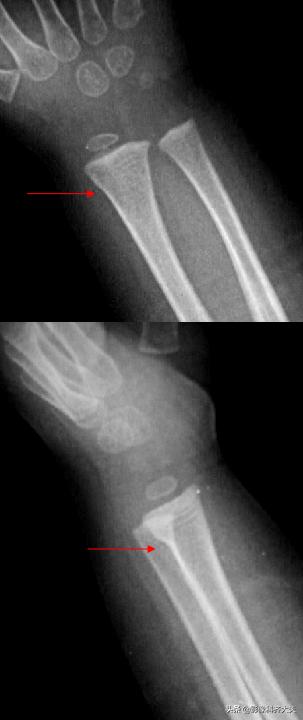

胫腓骨远端骨折

Colles骨折:伸展型桡骨远端骨折,在桡骨远端2-3cm以内的横行或粉碎骨折,远侧向桡或背侧移位,常合并尺骨茎突骨折。